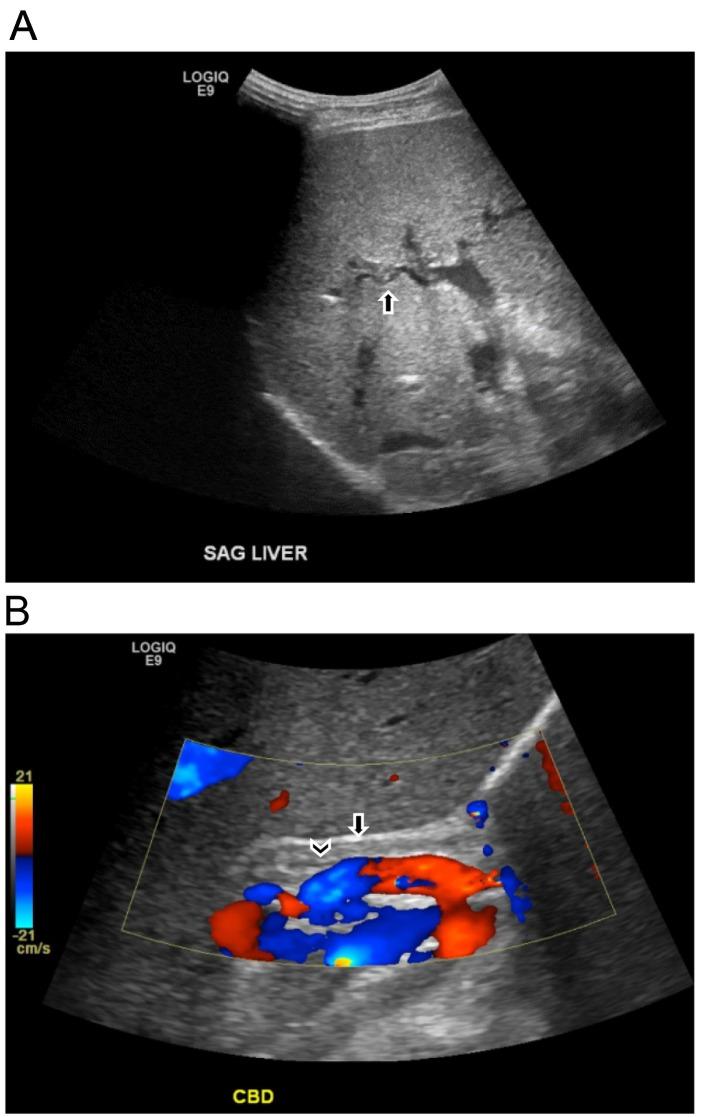

COVID-19 was first recognized by the World Health Organization (WHO) in December 2019 and declared a global pandemic in March 2020. Although COVID-19 primarily results in pulmonary symptoms, it is becoming apparent that it can lead to multisystemic manifestations. Liver damage with elevated AST and ALT is seen in patients with COVID-19. Although the etiology of liver damage is still debated, biliary damage is rarely seen. This case demonstrates a potential complication of COVID-19 in a previously healthy patient. The patient contracted COVID-19 in March 2020 and endured a complicated course including intubation, multiple readmissions, and chronic abdominal pain. He is now awaiting a liver transplant. Our case portrays biliary damage as an additional possible complication of COVID-19 and the importance of imaging in its diagnosis.

新型冠状病毒肺炎(COVID-19)于 2019 年 12 月被世界卫生组织(WHO)首次确认,并于 2020 年 3 月宣布为全球大流行。尽管 COVID-19 主要表现为肺部症状,但越来越明显的是,它可能导致多系统表现。COVID-19 患者会出现 AST 和 ALT 升高的肝损伤。尽管肝损伤的病因仍存在争议,但很少见到胆道损伤。本病例展示了一例既往健康患者 COVID-19 的潜在并发症。该患者于 2020 年 3 月感染 COVID-19,经历了包括插管、多次再次入院和慢性腹痛在内的复杂病程。他目前正在等待肝移植。我们的病例表明,胆道损伤是 COVID-19 的另一种可能并发症,影像学检查对其诊断具有重要意义。